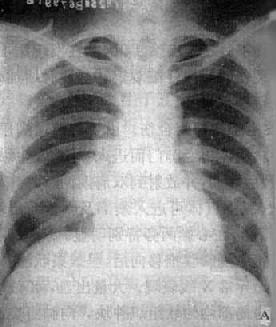

X线表现可多种多样,一般为陈旧性病灶周围炎,多在锁骨上、下区,表现为中心密度较高而边缘模糊的致密影(图3-1-10)。也可为锁骨下区出现新的渗出性病灶,表现为小片云絮状影,范围较大时可呈肺段或肺叶性浸润,症变的发展过程较为复杂,早期渗出性病变可以完全吸收,但一般多呈时好时坏的慢性过程,故可有渗出、增殖、播散、纤维和空洞等多种性质的病灶同时存在(图3-1-24)。

图3-1-24 左肺浸润型肺结核空洞形成

左肺上野第2前肋间边缘模糊的致密影,其中可见空洞